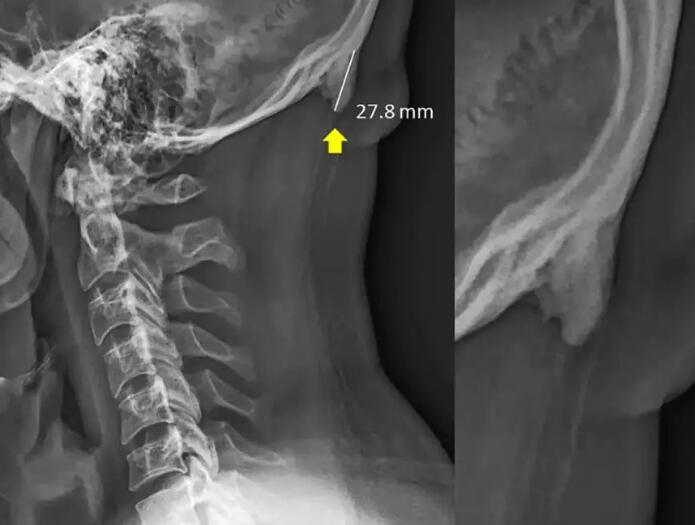

脑后生反骨:这里是指的后脑位置枕骨处凸起的2颗明显的骨头,剃短发时能看到,用手也可以摸到,这种情况是先天形成的。